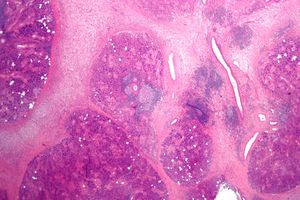

الغدد اللعابية Salivary gland هي غدد قنوية في الثدييات تفرز لعاب وهي تكوينات صلبة تتكون من ملايين الخلايا الإفرازية وتسري بين هذه الخلايا قنوات رقيقة تجمع اللعاب وتحمله وتوجهه إلى قناة مفردة تقوم بدورها بحمل اللعاب إلى الفم.

هي غدد قنوية في الثدييات تفرز لعاب وهي تكوينات صلبة تتكون من ملايين الخلايا الإفرازية وتسري بين هذه الخلايا قنوات رقيقة تجمع اللعاب وتحمله وتوجهه إلى قناة مفردة تقوم بدورها بحمل اللعاب إلى الفم.